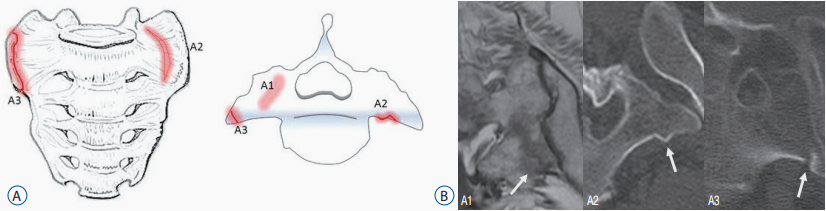

本田征象

骶骨机能不全骨折时骨折线通常垂直穿过骶骨翼,平行于双侧骶髂关节,在核医学 SPECT/CT 或 PET/CT 显像(冠状位重建)形似东风本田车标—大写字母「H」,故又称「Honda」征、东风本田征,为骶骨机能不全骨折较特异影像表现。

骶骨机能不全骨折分型

骶骨 A 型骨折

注:A 型-骶骨翼不全骨折 A1-单侧骨挫伤表现,未见明显骨折线 A2-骨皮质扭曲,无明显骨质破坏 A3-骶骨翼前外侧缘骨折(距骶髂关节小于 1 cm)